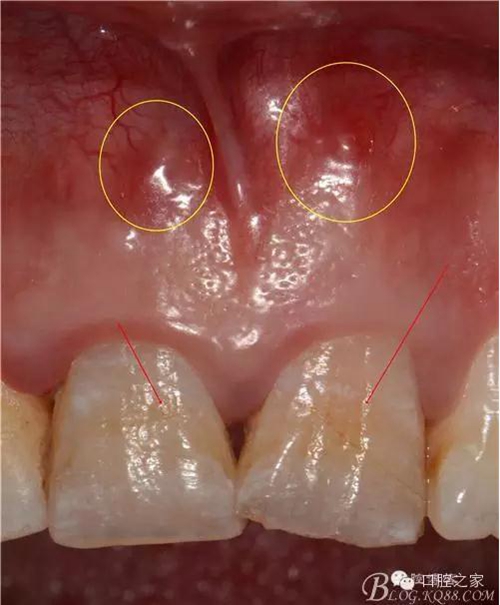

去髓術(shù)或根管治療后,由于某些原因使修復(fù)體與洞壁之間產(chǎn)生縫隙,含有細(xì)菌及食物碎屑的唾液通過(guò)充填不嚴(yán)密、根尖孔未封閉的根管進(jìn)入根尖周組織,導(dǎo)致根尖周炎或使原有炎癥加重,這種情況稱(chēng)冠向微滲漏二次感染。窩洞或根管充填不嚴(yán)密,組織液滲入其間稱(chēng)滲漏,根據(jù)進(jìn)入根管不同方向分為冠滲漏或根尖滲漏。有學(xué)者認(rèn)為:冠滲漏對(duì)去髓術(shù)及根管治療造成的影響比根尖滲漏更重要。這是因?yàn)椋汗跐B漏進(jìn)入的是帶有大量細(xì)菌的唾液,而根尖滲漏除了根尖周仍有含細(xì)菌的病灶外,正常的組織液滲入不一定會(huì)導(dǎo)致細(xì)菌繁殖。此外,微滲漏因細(xì)菌存在于缺少氧氣的環(huán)境,有利于厭氧菌的生長(zhǎng)繁殖,因而容易導(dǎo)致治療失敗。

產(chǎn)生冠向微滲漏的主要原因有以下幾種。